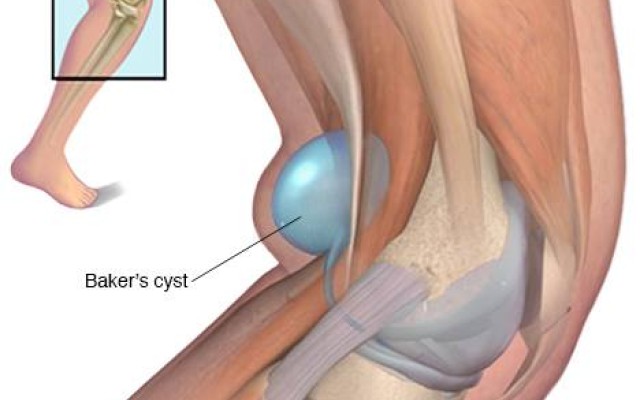

Posted in Dr Kaushik Hazratwala Blogs on Sunday, 16 July 2017 by Kaushik Hazratwala

A Baker's cyst is a fluid-filled cyst that causes a bulge and a feeling of tightness behind your knee. The pain can get worse when you fully flex or extend your knee or when you're active. Image courtesy - Mayo Foundation Read: 5 Steps to Finding the Perfect Life after Knee Replacement A Baker's cyst is usually the result of a problem with your knee joint, such as arthritis or a...Bilateral (2) Hip and Knee Replacements